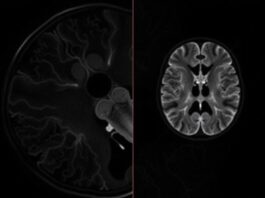

МРТ-ангиография: невидимая карта ваших сосудов, которую может сделать только магнит

МРТ-ангиография — это способ заглянуть внутрь сосудистой системы без скальпеля и без лучевой нагрузки. Она дает трёхмерную, детальную картину артерий и вен, помогает понять,...